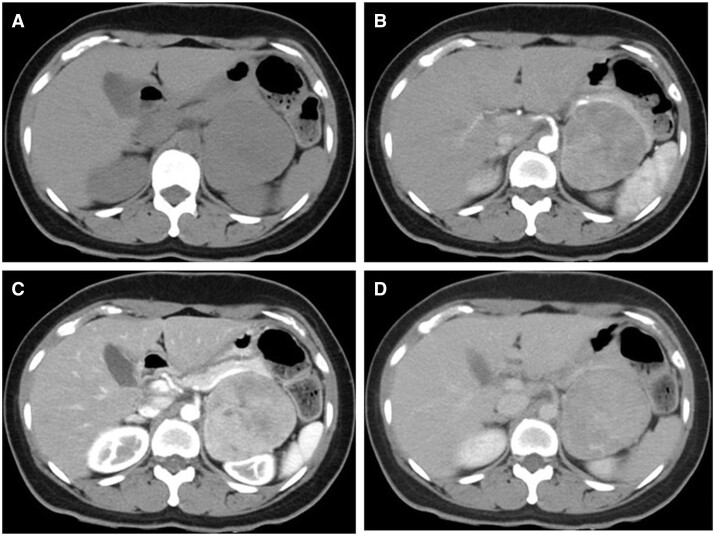

Oncocytoma is a tumour that predominantly occurs in the kidneys and salivary glands. Only approximately 200 cases have been reported to be of adrenal origin to date, and only a few reports about its radiological findings have been published so far. Herein, we present the CT and MRI findings of an adrenal oncocytoma observed in a patient suspected of having mitochondrial abnormalities, along with the pathological findings. The tumour was roughly classified into three areas: a hypercellular region, a region containing fibrous tissue, and an oedematous region. These corresponded to the restricted diffusion area on the apparent diffusion coefficient map, the gradually enhanced area at the secretory phase on contrast-enhanced CT scan, and the obvious hyperintensity on the T2-weighted image, respectively. We also discuss these findings in the context of previously reported radiological findings in the literature. Diagnosing adrenal oncocytoma through imaging is challenging, and it is crucial to consider the possibility of malignancy while making the differential diagnosis. Small-sized homogenous tumours may be hard to differentiate from lipid-poor adenomas, while larger inhomogeneous ones are hard to distinguish from adrenal cancer.

肿瘤细胞瘤是一种主要发生在肾脏和唾液腺的肿瘤。迄今为止,仅有约 200 例肾上腺来源的肿瘤被报道,而有关其放射学结果的报道也寥寥无几。在此,我们介绍了一名疑似线粒体异常患者肾上腺肿瘤的 CT 和 MRI 结果以及病理结果。肿瘤大致分为三个区域:高细胞区、含纤维组织区和水肿区。这些区域分别与表观扩散系数图上的扩散受限区、对比增强 CT 扫描中分泌期的逐渐增强区和 T2 加权图像上的明显高密度区相对应。我们还结合以前文献中报道的放射学结果对这些发现进行了讨论。通过影像学诊断肾上腺肿瘤细胞瘤具有挑战性,在进行鉴别诊断时考虑恶性肿瘤的可能性至关重要。体积较小的均质肿瘤可能很难与贫脂腺瘤相鉴别,而体积较大的不均质肿瘤则很难与肾上腺癌相鉴别。